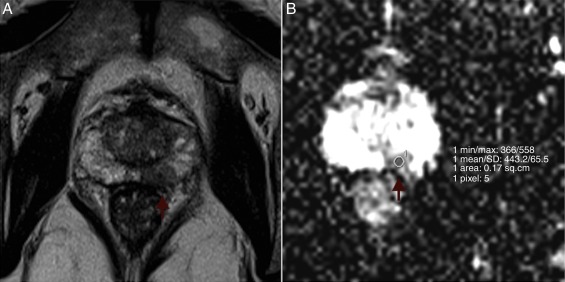

Mean ADCs were measured and examined for correlation with Gleason scores. The radiologist was blinded to the Gleason scores. All measurements were performed through the application of a single slice region of interest (ROI) within the tumor in the ADC map, trying to avoid tumor edges. ROIs had the same size for all tumors (27 mm2 ). In multifocal tumors, the two largest foci were considered for ADC measurement. In large, heterogeneous tumors, ROIs were placed in the darkest area of the tumor. Due to limitations in spatial resolution, tumors smaller than 5 mm in bigger axis were not studied. Fig. 1 shows an example of ROI placement. Among the 30 patients, 2 had multifocal pathology with volume enough to measure on the ADC map, so a total of 32 tumors were studied.

Example of ROI placement. Left peripheral prostate cancer in a 67-year-old man ...

Figure 1.

Example of ROI placement. Left peripheral prostate cancer in a 67-year-old man (PSA 9.5 ng/mL; Gleason Score of 8). (A) Axial T2-weighted MR image shows a left peripheral hypointense tumor (arrow). (B) ADC map reveals left suspicious hyposignal lesion and ROI placement (arrow).